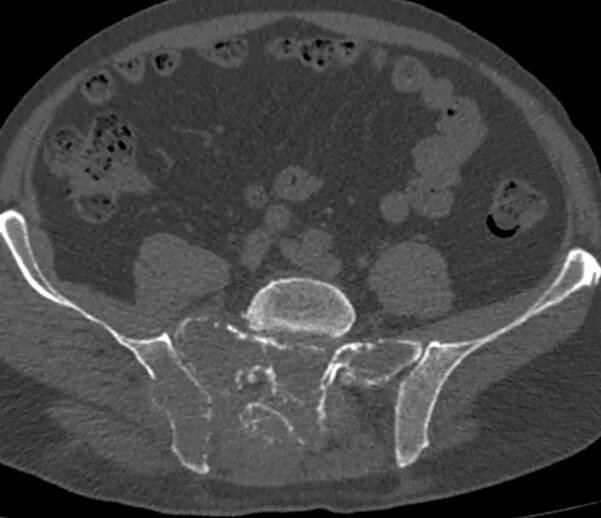

Метастазы в крестце